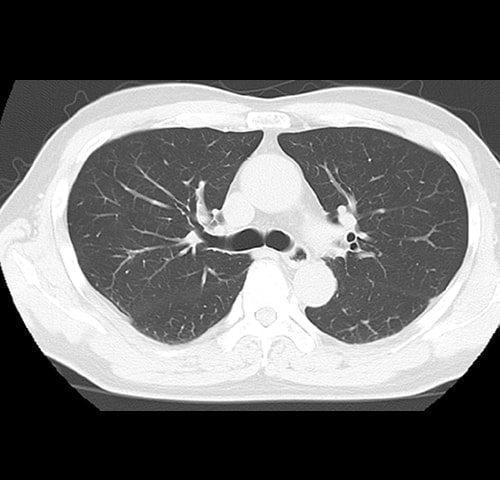

・ 肺(肺炎・肺気腫・ 肺がん)病変

肺